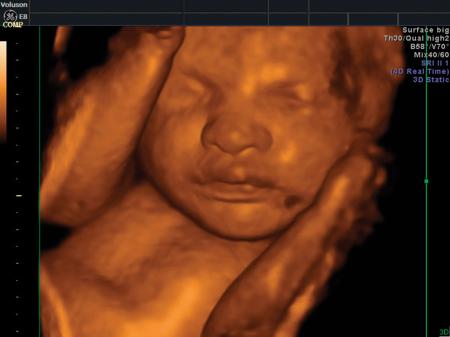

Fotografías de ecografías 4D HD/5D

Haga click sobre las imágenes para ampliar